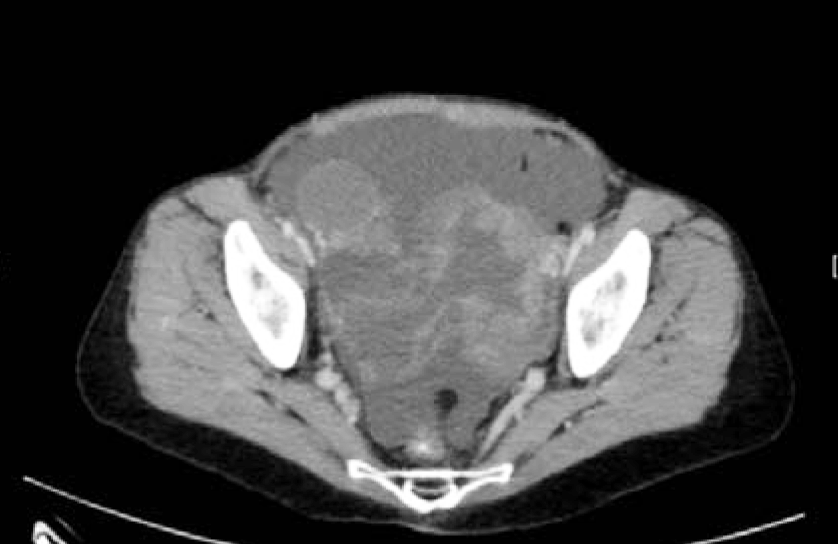

A 58-year-old female with no significant PMH, presented to the ER with acute onset abdominal pain, nausea, vomiting and diarrhea for one day. Patient was in her usual state of health eating and drinking normally, when she started having diffuse abdominal pain. Initially thought it was “gas pain”, but progressed to 9/10 pain throughout the day. Her pain was also accompanied by nausea, multiple episodes of vomiting and diarrhea. A CT abdomen pelvis revealed large bilateral pelvic masses obstructing the colon and ureters (Figure 6 and 7). Soft tissue nodules and ascites also present. Findings were most concerning for peritoneal carcinomatosis (Figure 8 and 9).

Figure 6: CT scan abdomen and pelvis. Large bilateral pelvic masses.

Figure 7: CT scan abdomen and pelvis coronal view. Large bilateral pelvic masses obstructing the colon and ureters.

Figure 8: CT scan abdomen and pelvis. Multiple liver and splenic implants.

Figure 9: CT scan abdomen and pelvis. Peritoneal implants suggestive of carcinomatosis.